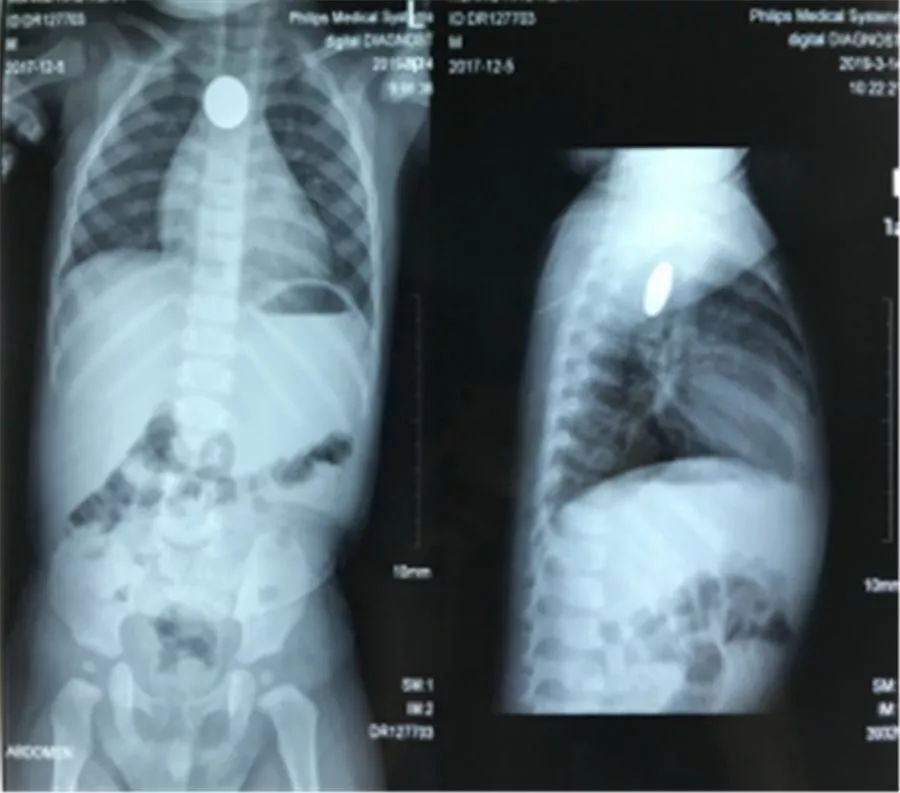

邝先生急匆匆地带孩子来到南方医科大学第五附属医院儿科就诊。经过胸片、腹部平片检查,考虑为食道异物,于是转诊到耳鼻喉科。耳鼻喉科主任欧阳绍基详细询问小孩的情况,通过认真体查和阅片,发现小轩轩的食管内有个圆形金属异物。

影像检查“照出”食管圆形金属片。